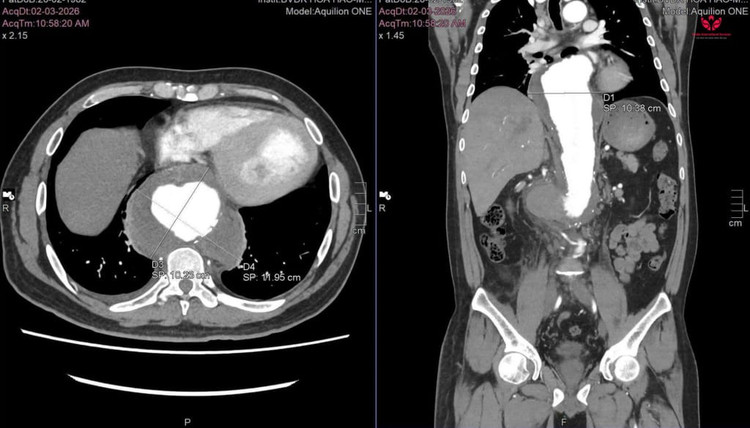

Anh L.Q.L (44 tuổi, ngụ tại Cần Thơ) nhập viện tại S.I.S Cần Thơ trong tình trạng đau bụng dữ dội. Qua kết quả khám và chụp CTA của bệnh viện tuyến trước, cho thấy anh L. đang trong tình trạng cấp cứu đe dọa tính mạng, phình động mạch chủ ngực – bụng đã vỡ kèm khối máu tụ lớn sau phúc mạc, đường kính khổng lồ lên đến 11cm.

Hình ảnh CT cho thấy kích thước khối máu tụ - Ảnh BVCC